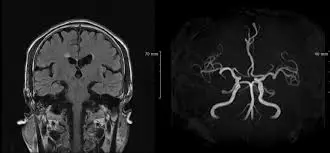

MR검사는 자기장과 고주파의 상호작용을 이용하여 인체의 해부학적, 병리학적인 정보를 얻을 수 있는 검사입니다. 뇌 MRI는 치매, 뇌종양 등 뇌의 구조적, 기능적 이상소견 여부를 확인하고자 하는 목적이 있으며 뇌MRA는 동맥류, 혈관기형, 혈관형태 등 뇌 혈관 이상을 확인하기 위해 혈관만을 영상화하는 검사입니다.

MRI(magnetic resonance imaging) : 뇌를 보는 검사 (구조)

MRA(magnetic resonance angiography) : 뇌혈관을 확인하는 검사 (혈관)

MRI(magnetic resonance imaging)는 뇌를 보는 검사이고, MRA(magnetic resonance angiography)는 뇌혈관을 확인하는 검사입니다. 상황에 따라 조영제 활용 여부가 결정됩니다.